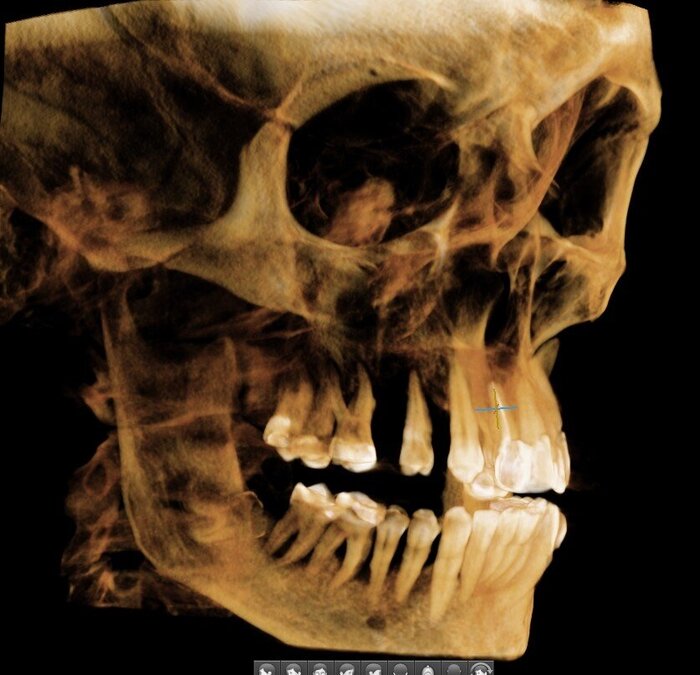

Делаем КЛКТ.

3Д визуализация костей черепа.

Так, мне уже всё понятно - хронический генерализованный пародонтит тяжёлой степени тяжести.